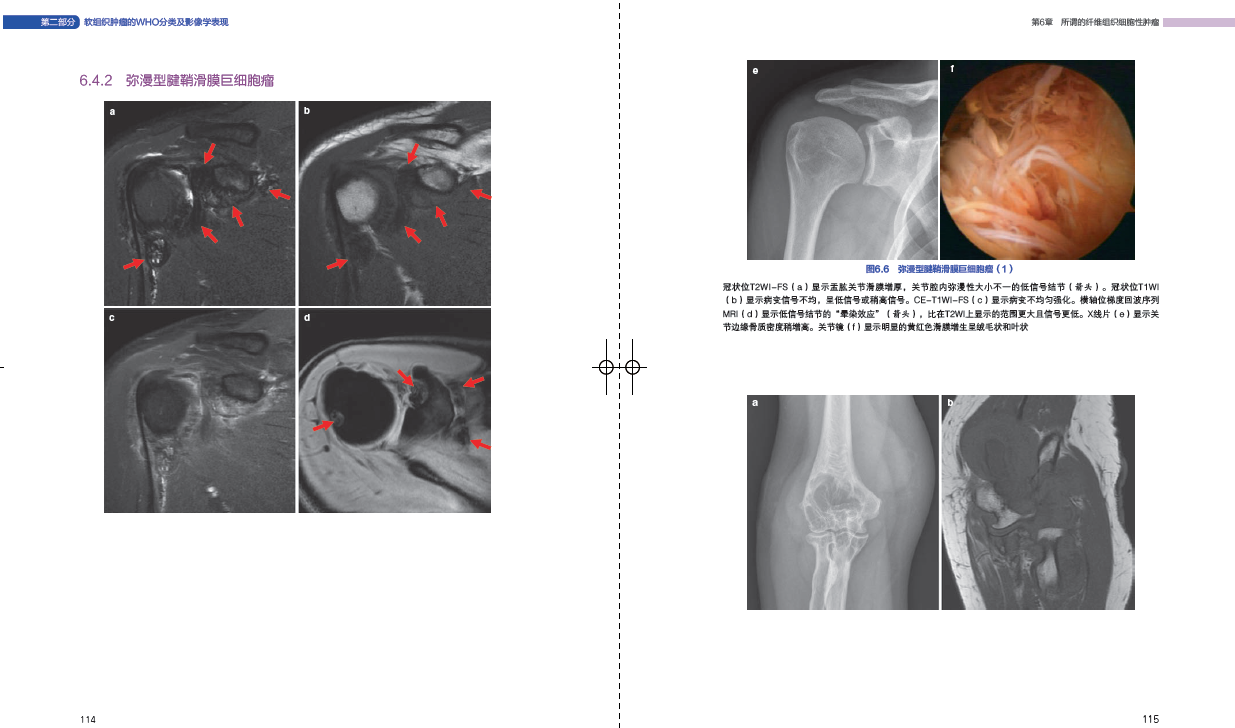

康亨植 广东科技出版 柳惠珍 软组织肿瘤病理临床诊断治疗病例软组织骨科肿瘤学 社9787535971654 高振华 肿瘤影像学软组织肿瘤